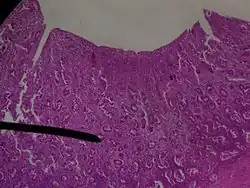

- Эндометрий (Слизистая оболочка) — образует внутренний слой стенок матки. Состоит из слоя цилиндрического эпителия, выстилающего поверхность и железы, и собственной пластинки соединительной ткани, связанной с миометрием. Она пронизана простыми трубчатыми железами, которые открываются на поверхность эпителия, самые глубокие их части достигают миометрия. Среди секреторных клеток рассеяны группки реснитчатых цилиндрических клеток. Эндометрий состоит из двух слоёв — поверхностного, толстого слоя, называемого функциональным, и глубже расположенного — базального слоя.

Шейка матки

Это относительно узкий сегмент матки, стенка которой состоит преимущественно из плотной коллагеновой ткани и лишь небольшого количества гладких мышц и эластической ткани. Канал шейки уплощён, а его слизистая оболочка состоит из высокого цилиндрического эпителия, продуцирующего слизь, и соединительнотканной собственной пластинки, которая представляет собой фиброзную соединительную ткань, содержащую клетки. На передней и задней поверхности канала имеются два продольных гребня и отходящие от них под острым углом более мелкие пальмовидные складки. Соприкасаясь друг с другом при впадении канала, пальмовидные складки препятствуют проникновению в полость матки содержимого из влагалища. Помимо гребней и складок в канале имеются многочисленные ветвящиеся трубчатые железы. Влагалищная часть шейки матки покрыта плоским неороговевающим эпителием, который обычно простирается на небольшое расстояние в шеечный канал, где переходит в характерный для него цилиндрический эпителий. Таким образом, у зрелых девушек и женщин граница перехода цилиндрического эпителия в плоский неороговевающий — гистологическая граница — соответствует наружному зеву шейки матки. У девушек же до 21 года цилиндрический эпителий может спускаться ниже границы наружного зева и заходить на влагалищную часть шейки, создавая картину эрозии шейки матки, поэтому подобный диагноз несостоятелен у молодых в силу естественных анатомических особенностей.